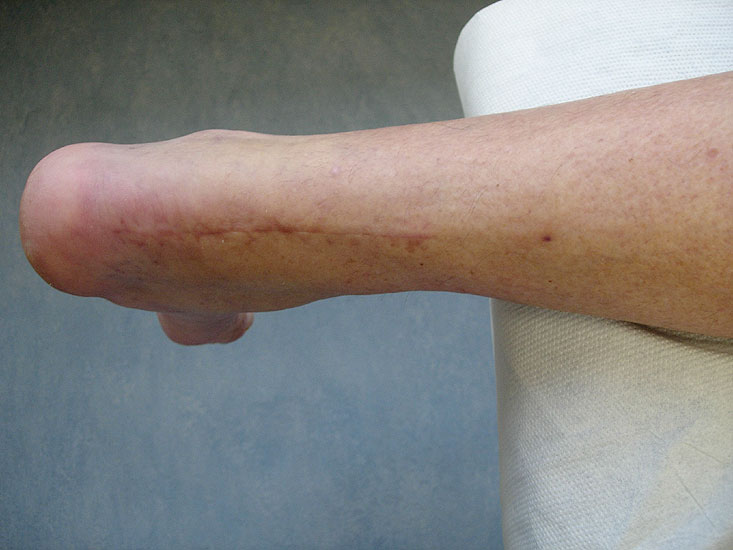

Langstreckige Defekte der Achillessehne stellen den Operateur oft vor große Schwierigkeiten, unabhängig davon, ob der Defekt durch mehrfache Rupturen, schwere degenerative Veränderungen des Sehnenmaterials oder durch eine Infektion nach Achillessehnennaht entstanden ist 1. Neben der Transposition des M. peronaeus brevis, die von Hepp und Blauth 1978 vorgestellt wurde 2, der immer eine Schwächung der Pronation und der aktiven lateralen Stabilisierung nach sich zieht, wurde die Transposition der Sehne des M. flexor hallucis longus zur Augmentation der Achillessehne erstmalig von Wapner 1993 3 beschrieben. Aufgrund der technisch einfachen Durchführbarkeit und den zuverlässig guten Ergebnissen hat sich dieses Verfahren gegenüber der Transposition des M. peronaeus brevis weitgehend durchgesetzt und wird heute von der Mehrzahl der Operateure eingesetzt.

Langstreckige degenerative Ruptur der Achillessehne.

• Langstreckige Defekte der Achillessehnen von >5 cm (Typ Myerson III) 6.

• Schwere, langstreckige degenerative Veränderungen der Achillessehne mit Ruptur (Abb. 1).

• Nach teilweiser oder vollständiger Resektion der Achillessehne bei Zustand nach Infekt.